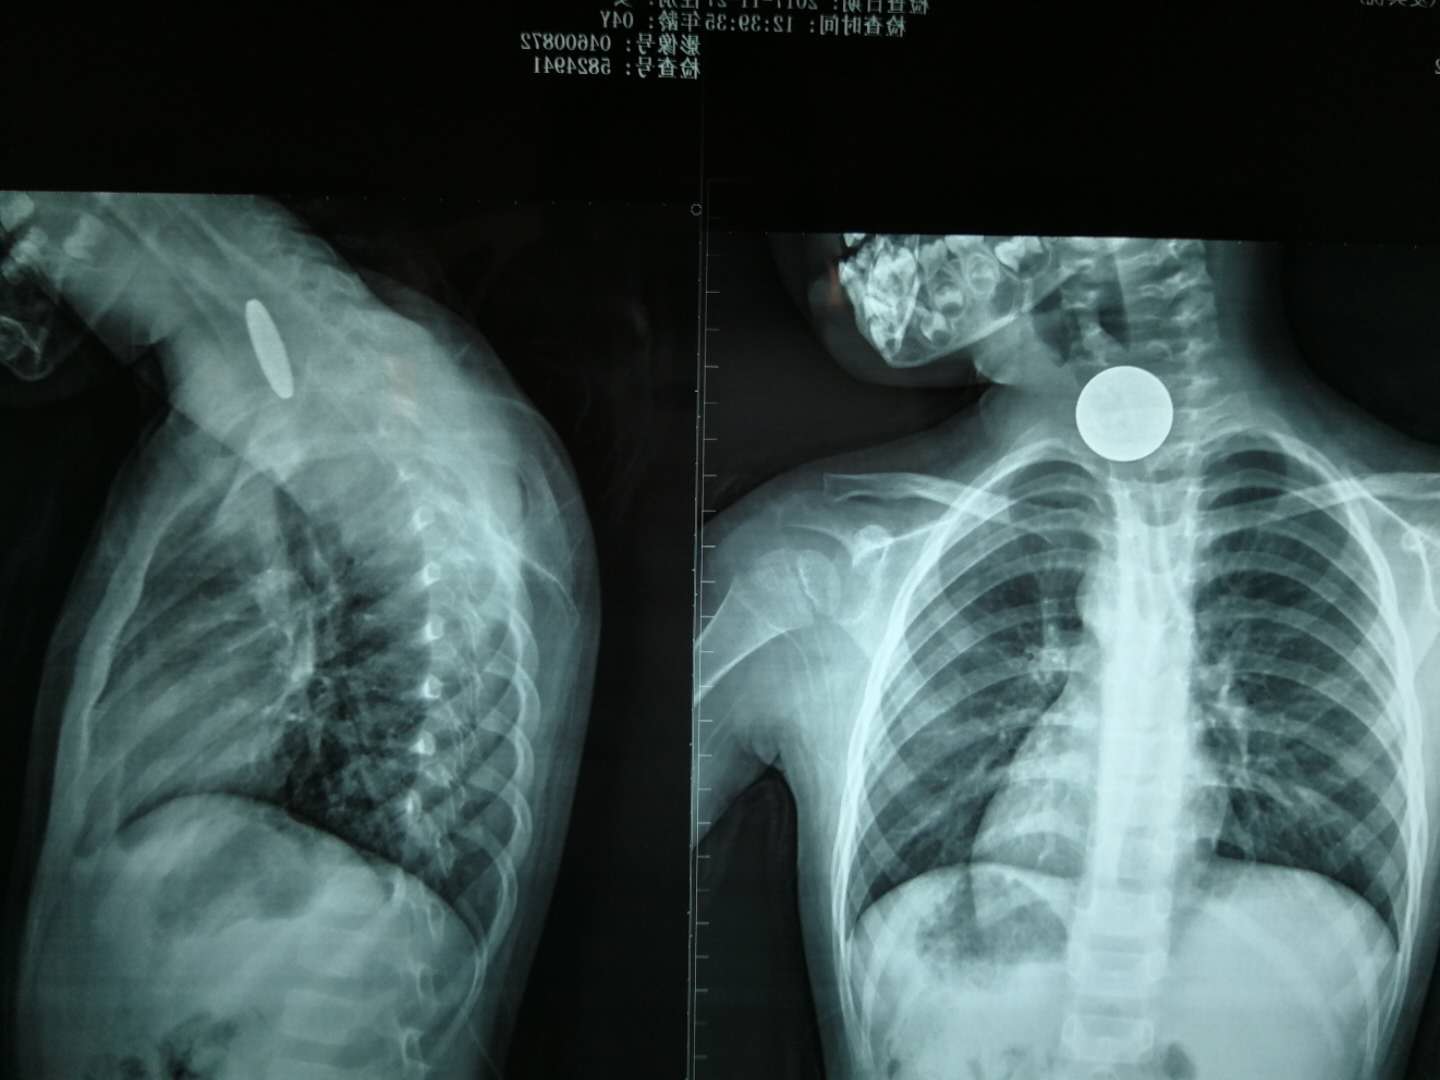

“醫(yī)生,快看看我的孩子!”這么焦急的聲音,到底發(fā)生了什么事?原來,11月27日上午11點,一個4歲的女孩獨自玩耍時不小心吞下了一枚1元硬幣,家長發(fā)現(xiàn)后立即將小孩送到我院急診科就診。在為女孩做了頸部和胸部的X光片檢查后,醫(yī)生發(fā)現(xiàn)硬幣卡在女孩的食道中間的狹窄段(注:非進食狀態(tài)下食道呈閉合狀)。